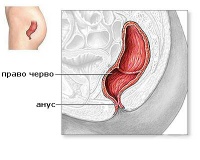

S36.6 Травма на право черво

Правото черво е защитено много добре и нараняването му се среща рядко, но все още често наранявания ...